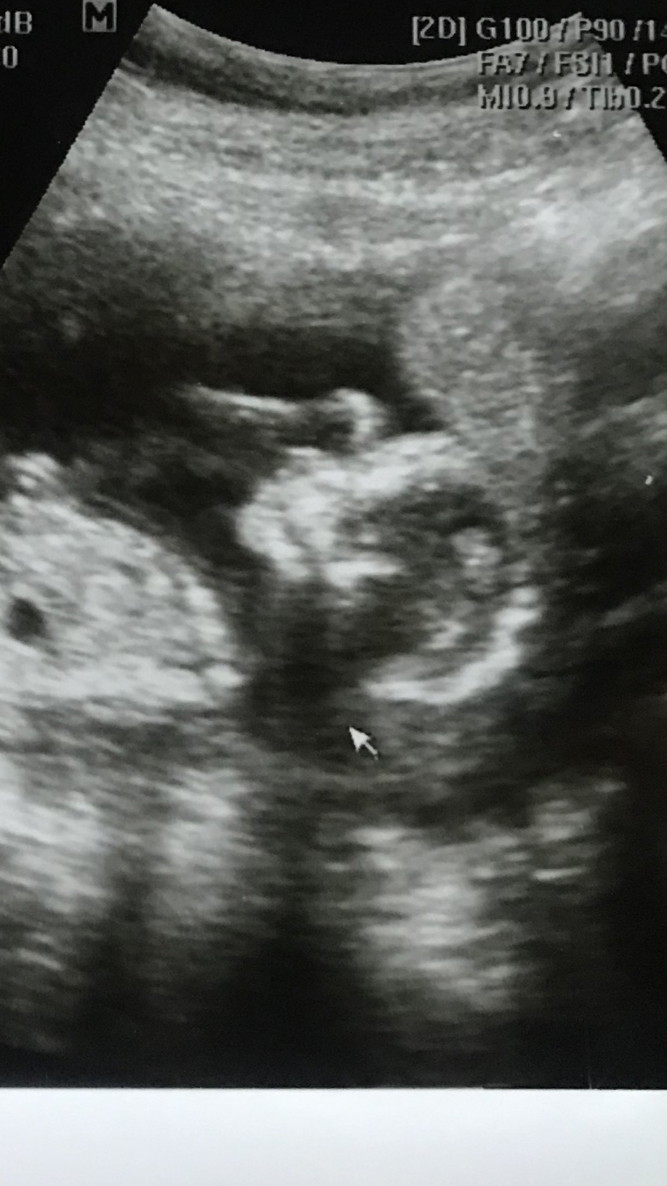

มีบ้านไหนซาวด์แล้วจมูกโด่งแบบนี้มั้ยคะ ออกมาจมูกน้องโด่งแบบนี้รึเปล่า? นี่คุณหมอบอกโด่งมาก?

จมูกโด่งมาก

โด่งมากค่ะ